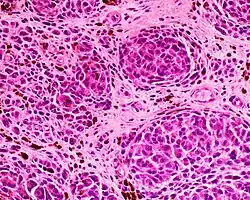

Histopathology

Epithelioid blue nevus Malignant blue nevus

Malignant blue nevus